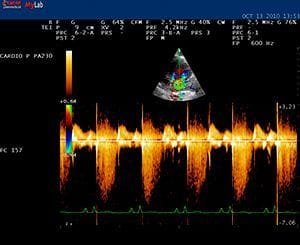

La ecografía se basa en la emisión de ultrasonidos, y al contrario que la radiografía y el TAC no emite ningún tipo de radiación ionizante, siendo absolutamente inocua para los pacientes. Además es una prueba rápida, económica y que, en general, no requiere la sedación del animal. Las imágenes se obtienen en tiempo real y desde diferentes ángulos que se pueden modificar durante el examen. Esto nos permite obtener mucha información tanto sobre la estructura de los órganos como sobre su funcionalidad y además obtener muestras de líquidos o tejido afectado (biopsia) para su posterior examen en el laboratorio. Es una técnica de elección para examinar los órganos abdominales, el corazón (ecocardiografía), los grandes vasos, el diagnóstico de embarazo y últimamente se utiliza cada vez más en el examen musculoesquelético.